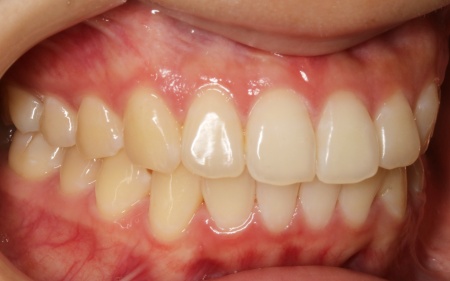

治療前

| はじめの相談内容 | 「歯並びが気になるので治療をしたい」とご相談いただきました。 |

| 診断結果 | 拝見したところ、上下の歯はデコボコに生えている状態でした。 このままでは見た目が気になるだけでなく、磨き残しが起こりやすくなることで虫歯や歯周病などの発症リスクが高まります。 以上のことから、歯並びを改善する矯正治療が必要だと診断しました。 |